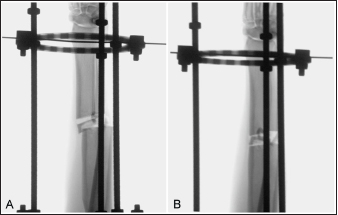

Fig. 3. Fluoroscopic images of a limb assigned to the medial plating group obtained after the application of the circular construct. The Kirschner wires were placed from cranial to caudal. Note that the distal fracture segment is cranially displaced after the radius and ulna had been distracted out to length (A). Manual pressure was applied to the cranial aspect of the distal radial segment to translate the segment caudally along the implanted Kirschner wire to improve sagittal plane alignment (B).

The total procedure time as well as incremental times for the subcategories of fixator placement, reduction, radial approach, and plate application did not differ between the cranial and medial plating groups (Table 1). Placement of the proximal Kirschner wire was more cumbersome than distal wire placement in both plating groups. Proximal cranial-to-caudal Kirschner wire placement was also more challenging than medial-to-lateral wire placement. Wire obliquity had to be addressed in four limbs in the cranial plating group and five limbs in the medial plating group. Obliquity was addressed by placing flat washers on one or both of the fixation bolts securing the Kirschner wire (n=1 limb in each plating group), attaching the fixation wire on opposite surfaces of the ring (n=1 and 2 in the cranial and medial plating group, respectively), or removing and replacing the wire (n=4 and 3 in the cranial and medial plating group, respectively). Lateral translation of the distal fracture segment along the Kirschner wire was performed to improve frontal plane alignment prior to plating in three limbs in the cranial plating group (Fig. 2). Caudal translation of the distal fracture segment along the Kirschner wire was performed to improve sagittal plane alignment prior to plating in two limbs in the medial plating group (Fig. 3). Obtaining sufficient exposure of the proximal radius to allow for plating required substantial tissue dissection, particularly in larger cadavers in both plating groups. The distal ring interfered with establishing a distal-to-proximal epiperiosteal tunnel in one limb in the cranial plating group, necessitating proximal-to-distal development. Plate orientation was more craniomedial than medial in six limbs in the medial plating group. Bone-holding forceps were used to improve reduction and alignment and to maintain appropriate plate position on the radius during plating in five limbs in the cranial plating group and six limbs in the medial plating group. Alignment was also similarly improved using bone holding forceps following initial plate placement by loosening then retightening or removing and replacing screws in four limbs in both plating groups (Fig. 4). The proximal or distal ring interfered with inserting the locking drill guide into the plate in three limbs in both plating groups. The fixator was removed in these limbs to allow placement of the final proximal or distal screw. Total and incremental procedure subcategory Likert scores assessing ease of performance did not differ between plating groups (Table 2). The number of fluoroscopic images (mean ± SEM: 8.7 ± 0.9 and 9.0 ± 0.8 for cranial and medial plating groups, respectively) obtained during the procedure did not differ between plating groups (p =0.77).